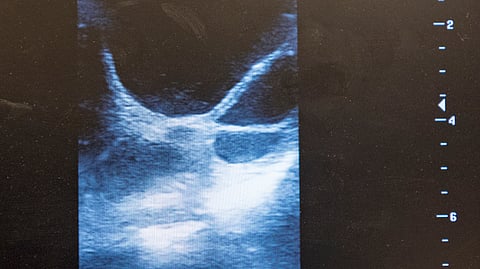

Kiimakontrollissa näkyvä iso omituinen möykky voi olla munasarjakasvain, mutta paljon useammin kyse on epäonnisesta follikkelista. Sellaisia syntyy joskus esimerkiksi kipulääkekuurin tuloksena..Useimmiten kasvaimet huomataan, kun halutaan ottaa selvää tamman kiiman vaiheesta, ja ultra paljastaakin jotain erikoista. Joskus munasarjoista osataan etsiä jotain erityistä tamman käytöksen takia. Koska tutkiminen tehdään ultralla, ei diagnosoiminen ole aivan helppoa. Myös oireet vaihtelevat..”Munasarjoissa voi olla hyvin monenlaisia rakenteita, eikä kasvaindiagnoosia saa kertaultrauksella tehtyä”, lisääntymistieteeseen erikoistunut eläinlääkäri Maria Kareskoski Saaren klinikalta kertoo..Monta ultrausta tarvitaan, koska diagnoosin takia tarvitsee tietää, mihin suuntaan epämääräisen asian koko muuttuu. .Tamman kohtu on kaksihaarainen ja kohdun molempiin sarviin liittyvät munanjohtimet ja munasarjat. .Normaalissa kiimassa molempiin munasarjoihin muodostuu follikkeli eli munarakkula, jonka sisällä on munasolu. Ultratessa mahdollisten follikkeleiden koko mitataan, ja follikkelin suunnitellaan siemennyksen ajankohta..Kun jotain ylimääräistä löytyy, vaihtoehtoja on useita. Iso rakenne hevosen munasarjassa voi olla esimerkiksi vain normaalirakenne, jossa hevosella on verekäs keltarauhanen (corpus hemorrhagicum)..Joskus taas kyseessä on epäonnistunut ovulaatio, eli ovulaatiossa on mennyt jokin pieleen ja tuloksena munasarjaan muodostuu hemorraginen anovulatorinen follikkeli..Nämä voivat olla varsin isokokoisia ja ne saattavat muistuttaa ulkonäöltään kasvainta. .Useimmiten hemorraginen anovulatorinen follikkeli on suurikokoinen, noin 4–12 senttiä pitkä, veren täyttämä rakenne, jota reunustaa voimakaskaikuinen eli ultrassa valkoinen kapea reunus, johon muodostuu keltarauhaskudosta..Ovulaatio voi epäonnistua monistakin syistä, mutta yksi voi olla kipulääkekuuri, jonka hevonen on saanut aiemman kiiman aikana..”Kun tutkimussyistä halutaan saada aikaan epäonnistuneita follikkeleita, niitä yritetään saada aikaan antamalla hevoselle fluniksiinia”, Kareskoski kertoo..Tällaisten rakenteiden normaali poistuminen vie viikkoja tai kuukausia, jos ihminen ei pyri vauhdittamaan sitä. .Kun hevoselta löytyy munasarjasta jotain ylimääräistä, sille annetaan yleensä ensihoitona kiimapiikki eli prostaglandiinia, sillä normaalit keltarauhaset, kasvaimet, ja anovulatoriset follikkelit saattavat toisinaan olla vaikeita erottaa toisistaan pelkästään ulkonäön perusteella..Anovulatorisia follikkeleita on kahta tyyppiä: toisessa on sisällä verta, toisessa rakenne on ontelomainen. Prostaglandiinin ansiosta anovulatorinen follikkeli tuhoutuu, mikäli siihen on jo muodostunut riittävästi keltarauhaskudosta, ja silloin normaalit kiimakierrot voivat jatkua..Haffit ja paffitEpäonnistuneet follikkelit, tammalääkärislangilla haffit ja paffit ovat melko yleisiä. Niitä tavataan tyypillisesti vanhoilla tammoilla, ja usein niitä muodostuu jostain syystä toistuvasti nimenomaan samoille tammoille..Kasvaimet sen sijaan ovat harvinaisia, vaikka niitä joka kesä löytyykin. Kaikkiaan hevonen on eläinlaji, jolla ei ole usein kasvaimia, toisin kuin esimerkiksi koiralla. .Joskus kyseessä on kuitenkin kasvain. Niistä yleisin on granulosasolukasvain. Se aiheuttaa usein muutoksia hormonitoimintaan, ja voi nostaa testosteronitasoa saaden tyypillisesti tammalle aikaan orimaista ulkonäköä ja käytöstä, joka voi olla hyvinkin vahvaa. Tamma saattaa esimerkiksi pyrkiä astumaan muita tammoja, ja se saattaa kasvattaa jyhkeän orikaulan..Joskus sillä on jatkuva kiima, toisaalta joiltain yksilöiltä kasvaimen myötä kiimat jäävät pois. .Usein nämä kasvaimet löytyvätkin silloin, kun tutkitaan hevosen käytöshäiriötä..Ylimääräinen hormonitoiminta vaikuttaa niin, että toinen, periaatteessa terve munasarja lakkaa toimimasta ja saattaa surkastua. .On myös muita kasvaintyyppejä, jotka eivät tuota hormonia. Nekin kuitenkin vievät tilaa, ja estävät follikkeleita kasvamasta. Näissä tapauksissa toisen puolen munasarja saattaa toimia normaalisti..Myös paiseen syntyminen munasarjaan on mahdollinen..Granulosasolukasvaimelle tyypillistä on, että se kasvaa, kun taas epäonnistunut follikkeli ajan kanssa surkastuu..Diagnosointia jatketaan ultraamisen lisäksi myös hormoniverinäytteellä. Kasvainsolut tuottavat anti-Müllerian hormonia, inhibiiniä, ja usein myös testosteronia, eli jos näiden hormonien pitoisuudet ovat korkeita, on kasvain todennäköisempi. Hevosen AMH-arvon mittaaminen maksaa noin 200 euroa..Asiasta hankalan tekee se, että aina hormoniarvotkaan eivät aina kerro varmasti, onko kasvainta vai ei. Aikaakin tutkiessa kuluu, sillä AMH-testi saattaa ottaa kolmekin viikkoa. Leikkaus?.Jos hevosella on granulosasolukasvain, se kannattaa poistaa. Tyypillisesti kasvain kasvaa koko ajan, ja mitä suuremmaksi se tulee, sitä vaikeampi poistaminen on tehdä. Siinä kun epäonnistunut follikkeli voi olla nyrkin kokoinen, kasvain voi kasvaa jalkapallon kokoiseksi..Kasvaimen kanssa poistetaan myös munasarja. Jäljelle jää kuitenkin vielä toinen, ja normaalitapauksessa se alkaa toimia pian normaalisti. .Sairaslomaa leikkaus tuo 4–6 viikkoa. Hormonitoiminnan palautuminen voi viedä kahdeksasta kuukaudesta vuoteen, mutta Kareskoski kertoo, että usein siementämäänkin saatetaan päästä saman kesän puolella..Kasvain ei välttämättä suuresti haittaa hevosta, mutta jos se on iso, se saattaa hyvinkin aiheuttaa epämukavuutta ja kipua. Lisäksi se roikkuu ylhäältä kiinnityskohdastaan, mikä voi tuntua epämiellyttävältä. Lisäksi käyttäytymisoireet voivat hankaloittaa hevosen käyttöä..Leikkaus tehdään yleensä kyljen kautta seisovalle hevoselle, ja varautua saa useamman tonnin hintaan..Joskus joudutaan vielä isompaan leikkaukseen, ja hevonen joudutaan kaatamaan ja poistamaan kasvain keskilinjasta. .Jos tammaa ei ole tarkoitus tiineyttää, kasvainta voi yrittää pienentää lääkkeellisesti GnRH-rokotteella, eli Improvacilla. Mikäli oireet palaavat tai kasvaimen kasvu jatkuu uudestaan GnRH-rokotussarjan jälkeen, lääkitys voidaan uusia.